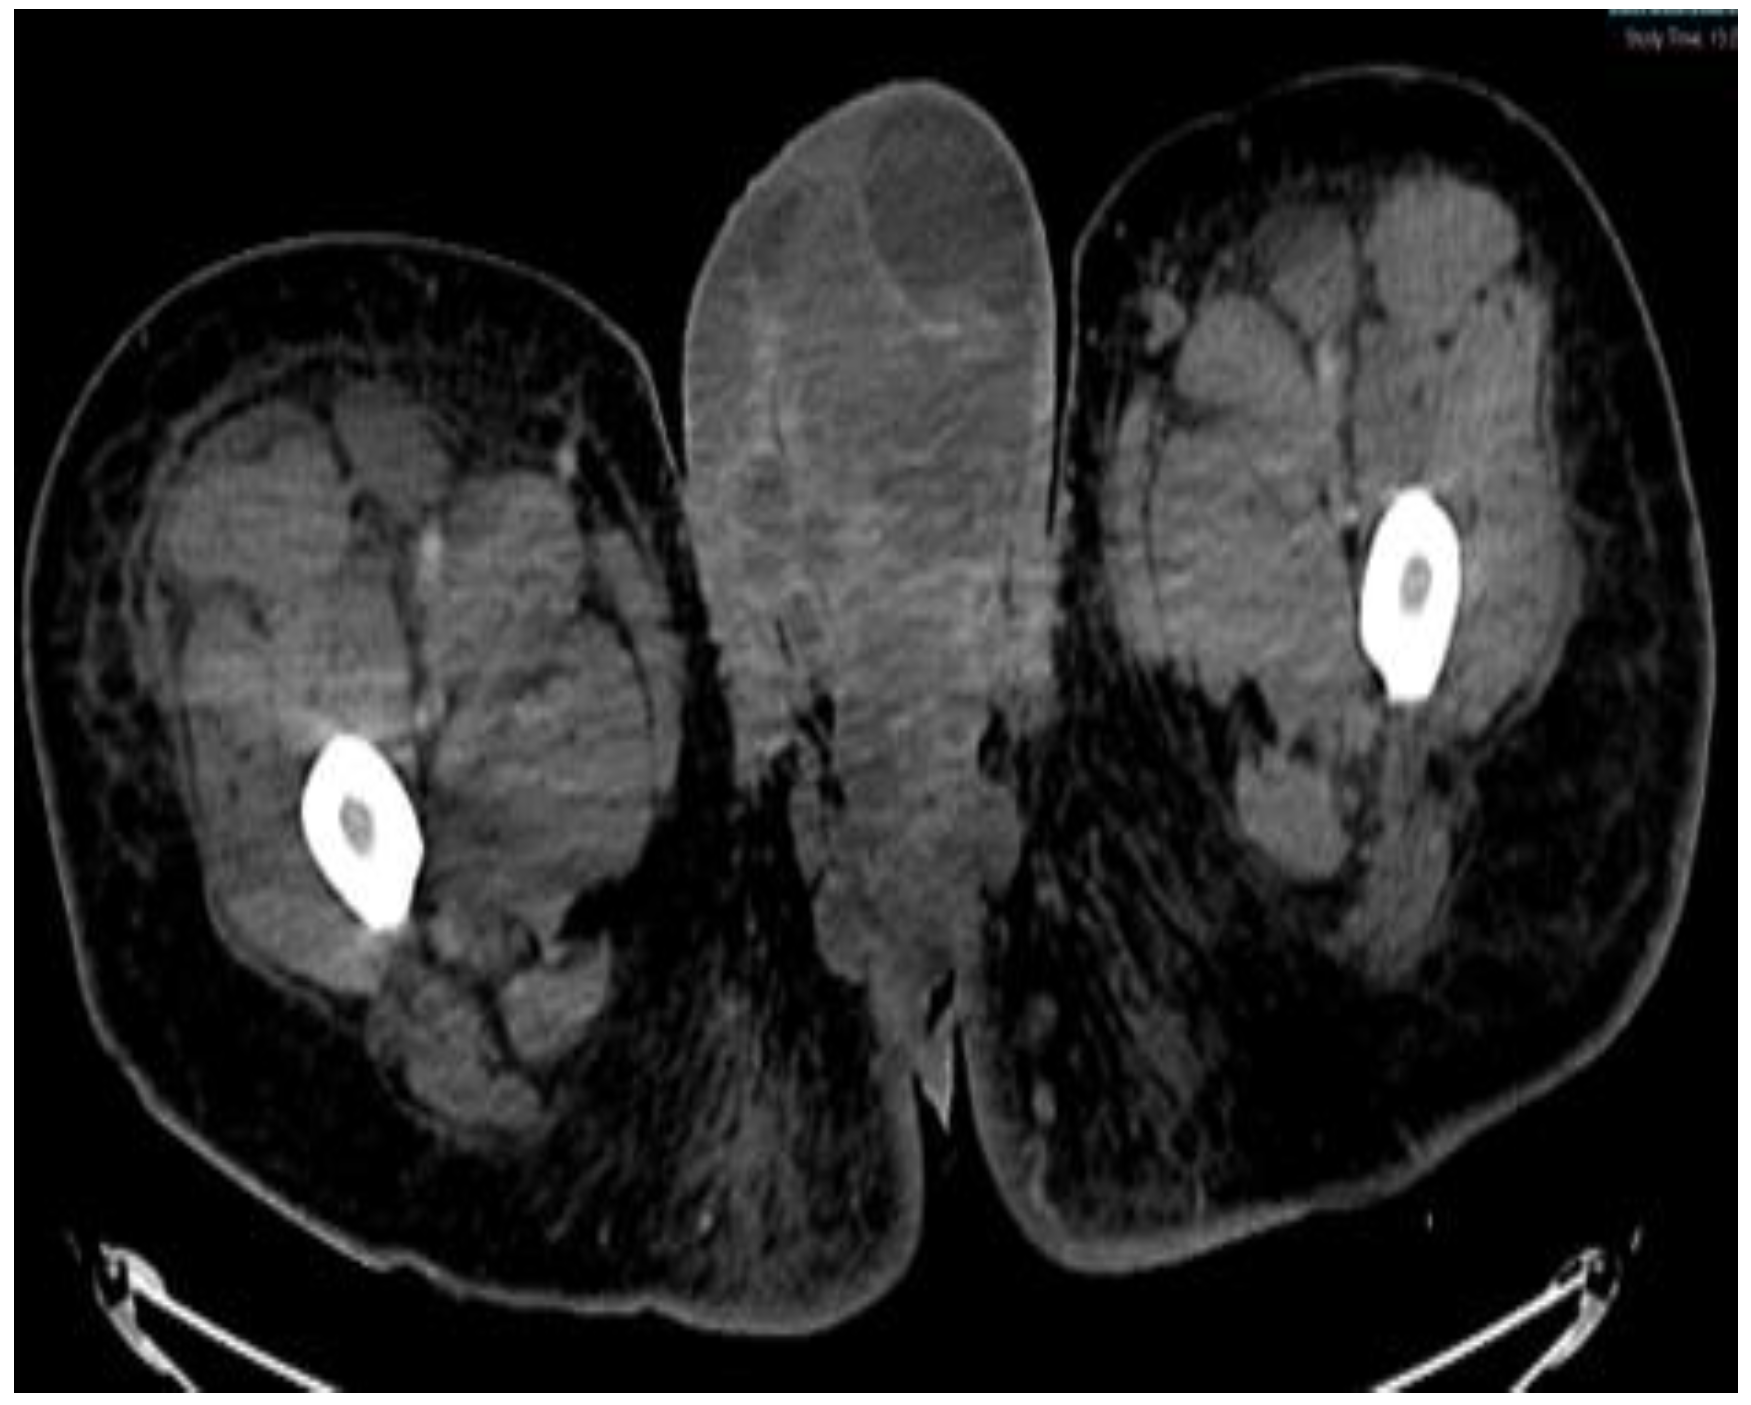

Figure 6.

CT scan in the axial view, abdominal window, showing scrotal mass extending through the anus with involvement of ischial tuberosity.

Figure 7.

CT in the coronal view of scrotal mass in the right inguinal lymph node.